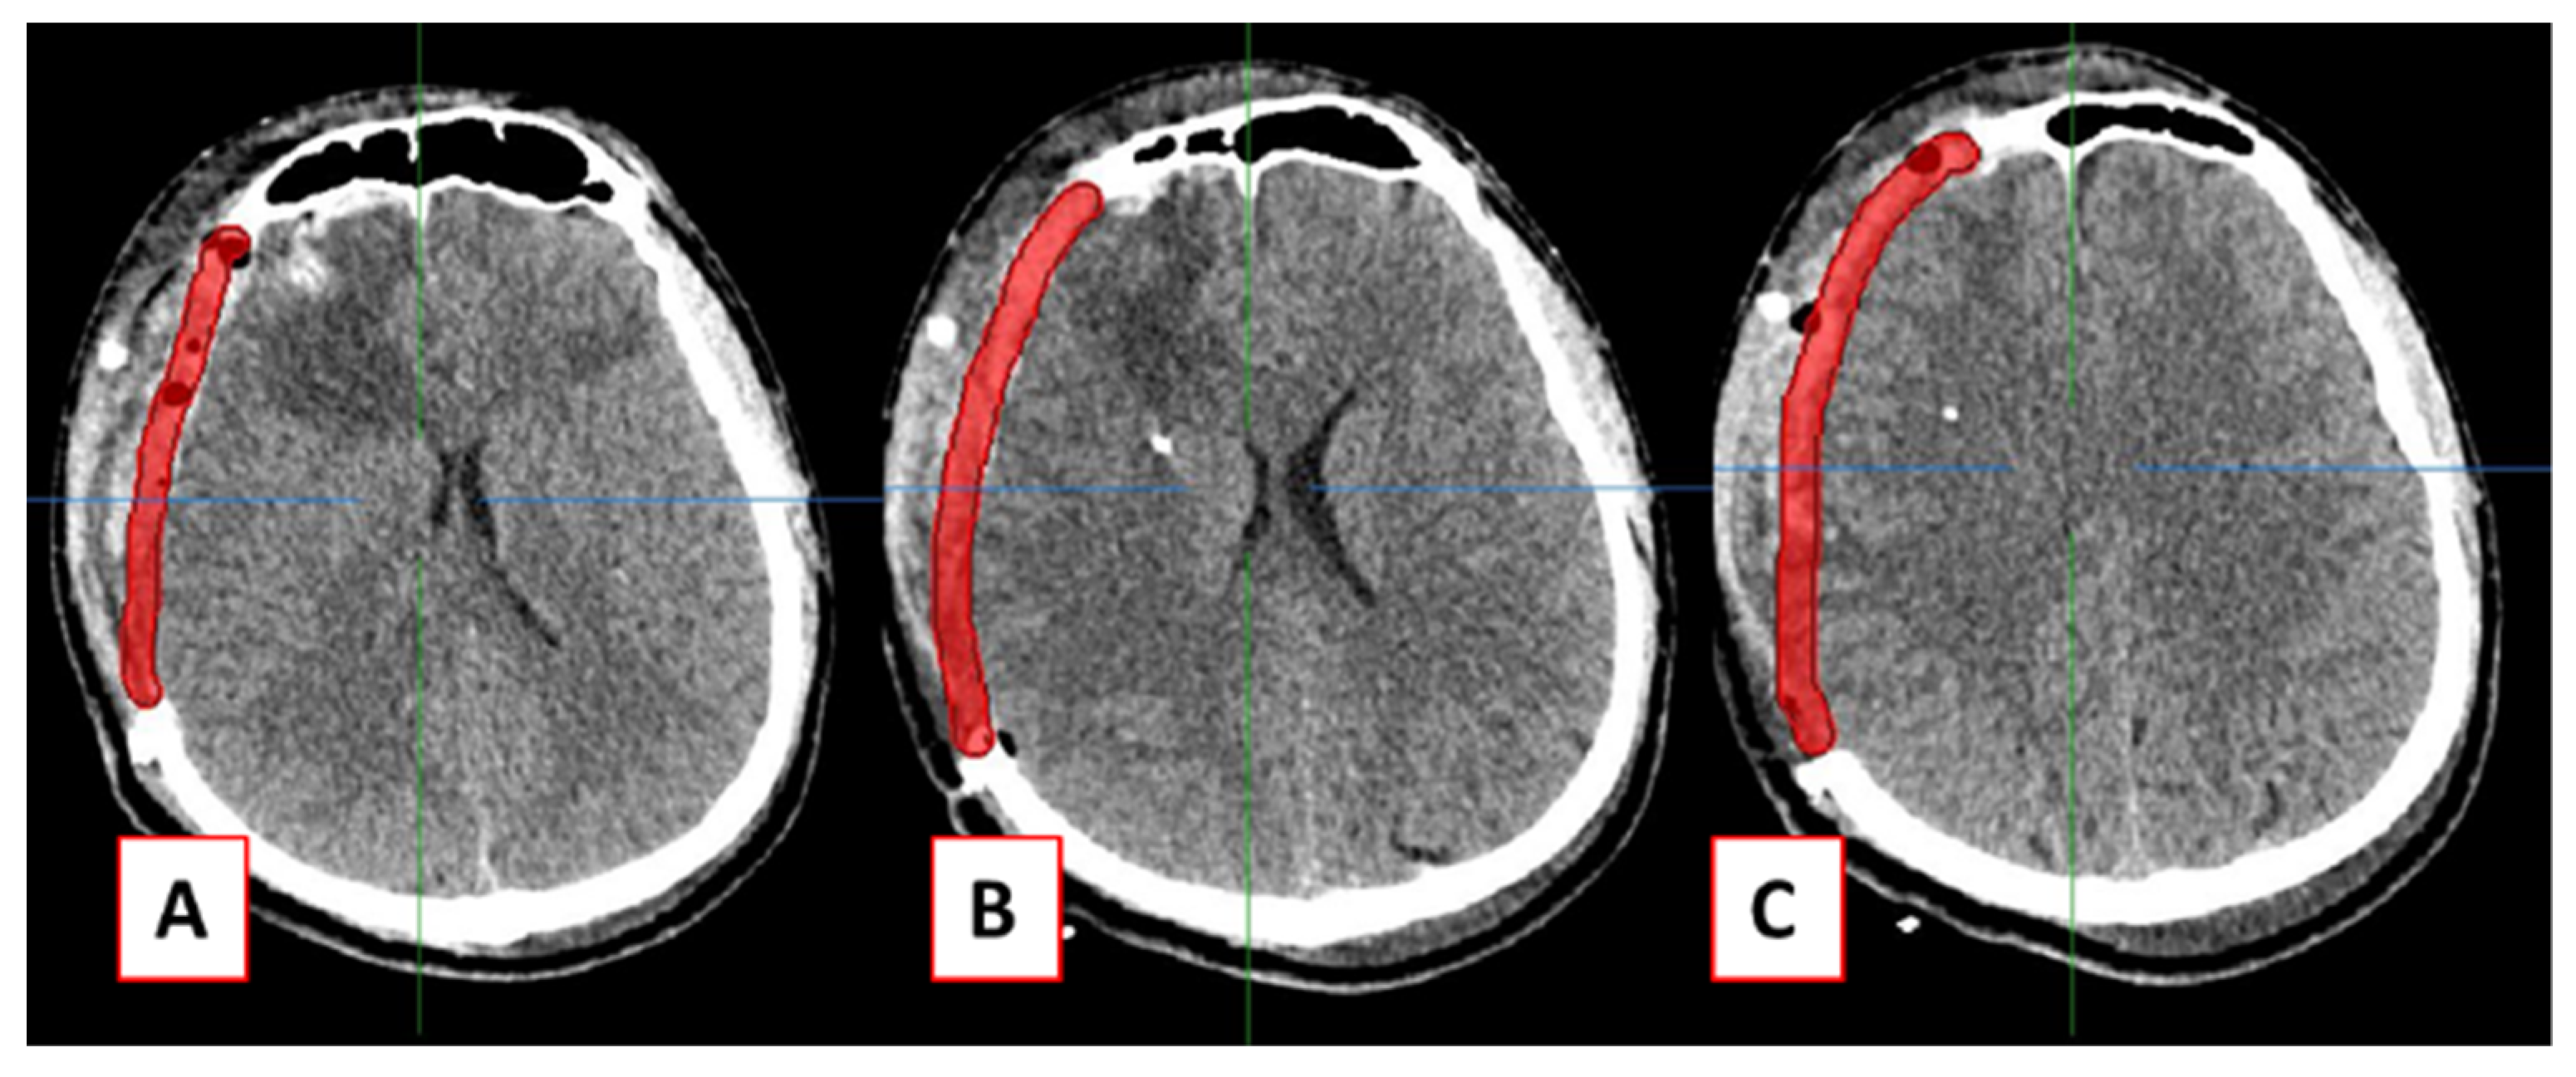

2.2. Design of Cranial Implants Using MITK Software